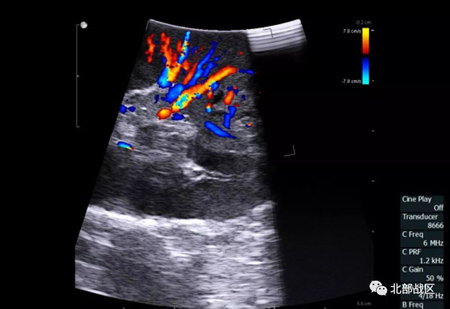

“检查中发现,小张右肾内肿瘤的位置很刁钻,且直径不到1.5厘米,通过以往外科手术治疗方式很难探查到。”泌尿外科副主任医师曹志强告诉记者,术前,他们与数字化医学转化中心联系,采用MR混合现实技术对肾脏形态及内部结构实施数字化重建,通过佩戴混合现实眼镜,透过肾脏确认肿瘤位置。

一场跨越千里的手术正如期进行,场面堪比科幻大片:该院启用了国际领先的星联远程手术会诊系统,与远在北京的解放军301医院建立实时连接。301医院专家佩戴的专业眼镜,仿佛拥有透视眼,直接“来到”手术室、“进入”腹腔镜视野中,对手术进行全程指导。与此同时,为更好的保全病人肾脏功能,术中还采用了血管分支阻断技术,通过数字化血管成像技术,对肿瘤供应动脉进行精准判定,由该院手术医生采用超声术探头对肿瘤血管实施成功阻断。